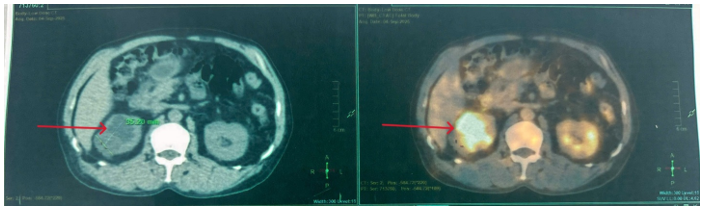

Hình 5: Hình ảnh đài – bể thận phải giãn độ II, còn sonde JJ niệu quản – bàng quang, nang thận phải đường kính 35mm